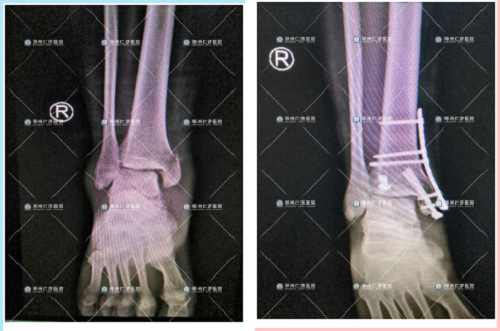

第二次手术成功进行

取内固定前、后

此次的取内固定手术,依旧是谷国俊副主任亲自为刘先生进行,手术很顺利,正在外十科的病房进行后续的观察。

取内固定术后,谷国俊副主任

查看恢复情况